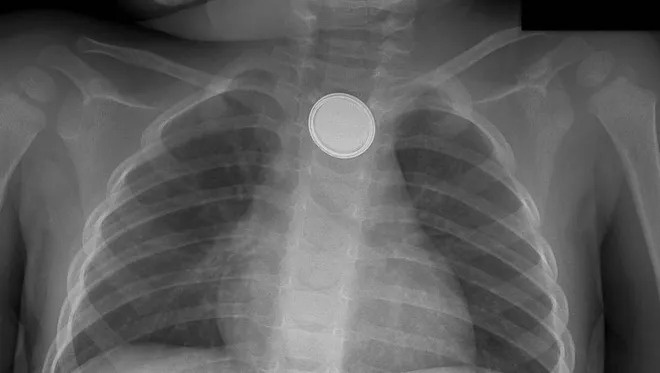

Hơn 70.000 trẻ em phải cấp cứu vì nuốt pin từ 2010 - 2019. Ảnh: The Star.

Pin cúc áo vẫn có thể gây ra biến chứng cho thực quản trẻ em ngay cả khi đã bị gắp ra. Ảnh: USA Today.

Nếu soi thấy một viên pin trong thực quản, ngay lập tức nó phải được lấy ra bằng phương pháp nội soi hoặc phẫu thuật, vì thực quản có thể bị tổn thương nghiêm trọng trong vòng ít nhất 2 giờ. Nhưng vết thương vẫn có thể phát triển ngay cả sau khi pin được lấy ra, dẫn đến các biến chứng tương đối hiếm gặp như liệt dây thanh quản hoặc rò khí quản.